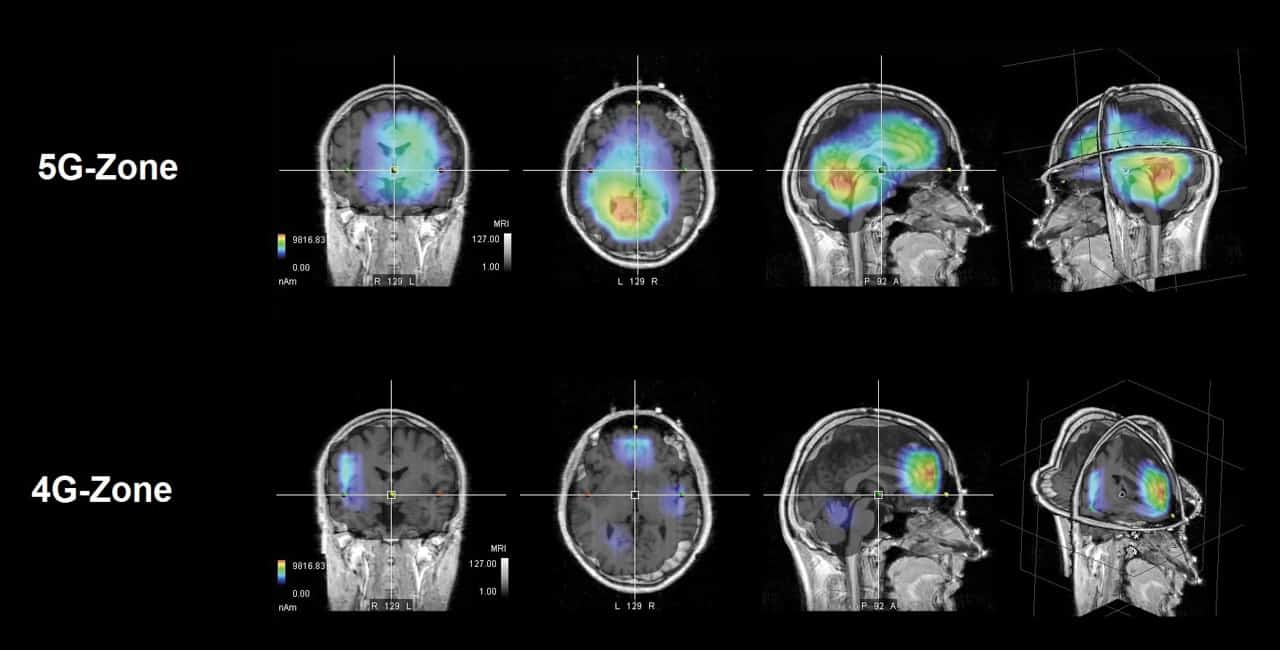

Mit der HRV lassen sich Stress und chronischer Stress erkennen. Die chronische Aktivierung des sympathischen Nervensystems führt zu Regulationsstörungen im gesamten Organismus, u. a. der Verdauung. Verdauungsprozesse werden unter Stress massiv eingeschränkt. Dadurch wird die Aufnahme von Nährstoffen beeinträchtigt und das Risiko für Mangelerscheinungen steigt. Eine dauerhafte Unterversorgung mit Mikronährstoffen führt schliesslich zur Entstehung von stoffwechselbedingten Zivilisationserkrankungen. Um Hinweise auf die gesundheitlichen Auswirkungen von Elektrosmog auf den menschlichen Organismus zu erhalten, werden mit einem ganzheitliche Analyse-System Daten errechnet, die u. a. auf der HRV beruhen. In Untersuchungen konnten dabei auch die schützenden Effekte einer Entstörungs-Technologie (Gabriel-Chip) dokumentiert werden – dargestellt als Reduzierung der Stressmarker, der Verbesserung des biologischen Alters und einem individuellen Elektrosmog-Belastungswert. Anhand der Anteile von Stressoren, die typischerweise unter Einwirkung von elektromagnetischer Strahlung auftreten, lassen sich so Aussagen über die individuelle Belastung treffen.